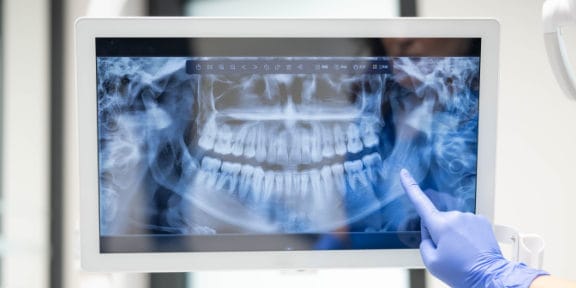

Digital X-Rays

Our office uses the latest in digital x-ray technology. Digital x-rays offer a detailed image of your entire mouth and also offer up to 80% less radiation than traditional film x-rays.

X-rays play an invaluable role in the diagnosis of dental problems, as well as provide a clear picture for a dentist to accurately diagnose and provide the necessary treatment.

We place a small sensor in your mouth. The sensor is connected to a computer by a thin wire. Next, an x-ray beam is sent through your teeth and into the sensor, which records the image of your teeth and sends it to the computer. The sensor can then be repositioned to image other sections of your teeth.

The digital dental x-ray system is more sensitive than dental x-ray film systems, so your exposure to x-rays is cut by as much as 90 percent. The large and color-enhanced images let you see what your dentist sees, so it's easier for you to understand how your dentist will treat your teeth. Your dental checkups take less time, and it's fun to watch this system work! Most patients are amazed.